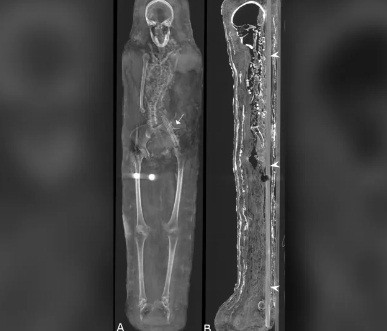

Kết quả kiểm tra cho thấy 2 xác ướp này qua đời vào khoảng năm 30 trước Công nguyên đến năm 395 sau Công nguyên.

Hai người này qua đời khi còn khá trẻ. Trong khi người đàn ông cao 1,64m qua đời khi khoảng 25 - 30 tuổi thì người phụ nữ có chiều cao 1,56m chết khi 30 - 40 tuổi.

Tuy nhiên, hiện các chuyên gia chưa thể tìm ra nguyên nhân tử vong của họ. Các chuyên gia mới phát hiện người phụ nữ gặp một số vấn đế về sức khỏe, trong đó có bệnh viêm khớp.